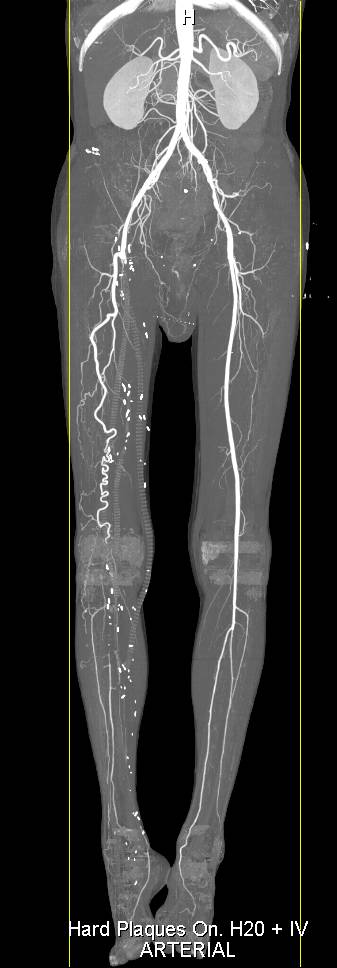

Aortic Aneurysm with Reconstruction of the Thoracic Aorta as well as Bypass Grafts